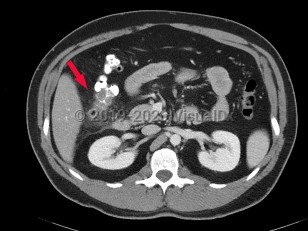

Diverticulitis is a disease characterized by inflammation in colonic diverticula. Cases are classified as uncomplicated or complicated on the basis of clinical and radiographic features. Uncomplicated cases are characterized by clinically stable patients with inflammation in a localized area of the bowel wall. By contrast, complicated disease is defined by the presence of abscess, phlegmon, fistula formation, obstruction (large bowel, small bowel), bleeding, perforation, or peritonitis, which are collectively present in about 12% of cases.

Patients classically present with abdominal pain (typically left lower quadrant), nausea and/or emesis, and fevers. Changes in bowel habits including loose, sometimes bloody bowel movements, as well as constipation, can occur. The prevalence is strongly associated with age and is most common in adults aged older than 50 years, although the incidence in younger populations has increased steadily in recent decades.